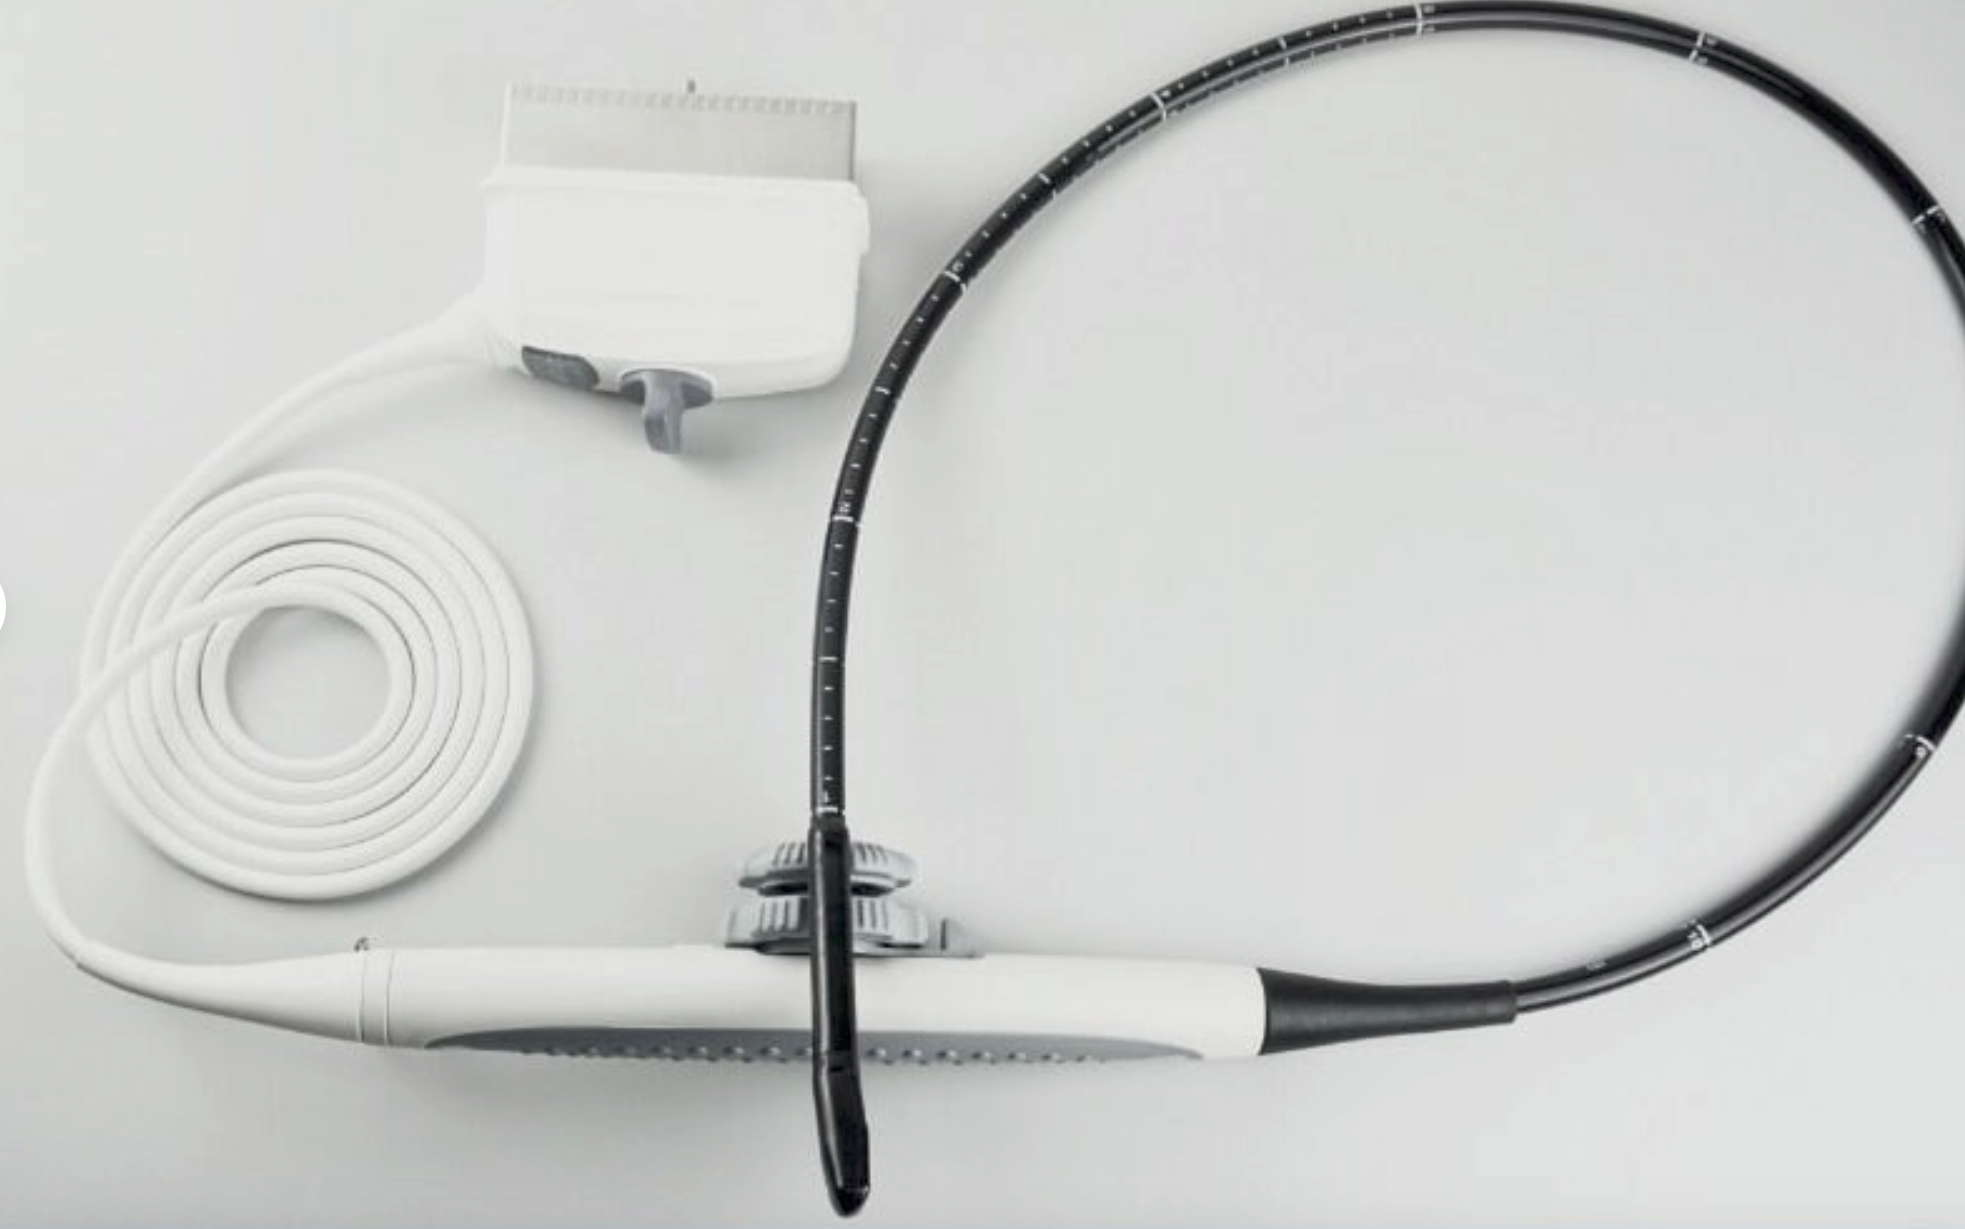

Probe Function: 3.5MHZ convex, abdominal organs

Probe 2: 7.5MHZ Transvaginal probe:gynecologic examination

The ultrasound scanner is a crucial tool in modern healthcare, particularly for monitoring pregnancy. Equipped with both convex and transvaginal probes, it provides exceptional 3D imaging capabilities. This means doctors can obtain clearer, more detailed images of the fetus, helping in making informed decisions regarding prenatal care. Because the images are so precise, healthcare providers can detect potential abnormalities early, enhancing the safety of both mother and child.